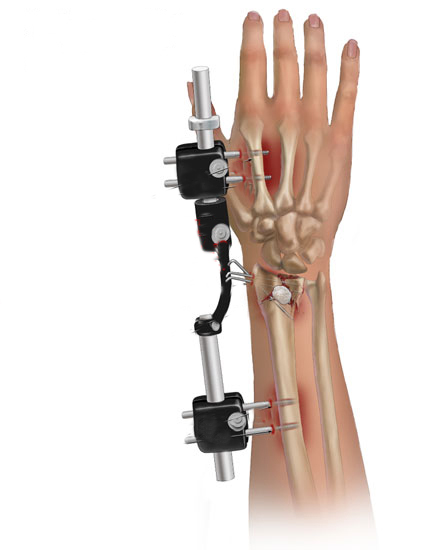

Fissatore Esterno

Per Fissatore Esterno s’intende un mezzo di fissaggio che non viene coperto dalla pelle ma attraverso piccole aste metalliche chiamate “fiches”, che vengono applicate sopra e sotto alla frattura nell’osso e un corpo centrale che serve a stabilizzare la frattura ossea. A volte in base al trauma viene associato ad altri sistemi di fissaggio come ad esempio i fili di Kirschner.

Il fissatore esterno può anche essere un mezzo di sintesi temporaneo ovvero quando la qualità dei tessuti molli è scadente si posizione per poi essere sostituito con un impianto interno come la placca e le viti.

Lo svantaggio di questo sistema chirurgico rispetto all’osteosintesi con placca e viti è l’infezione delle viti metalliche che fuoriescono dalla pelle, l’impossibilità di ridurre accuratamente la frattura e l’impossibilità di eseguire le mobilizzazioni precoci, mentre il vantaggio è la non esposizione della frattura.

![]() |

|

Fissatore Esterno utilizzato nel Cane |